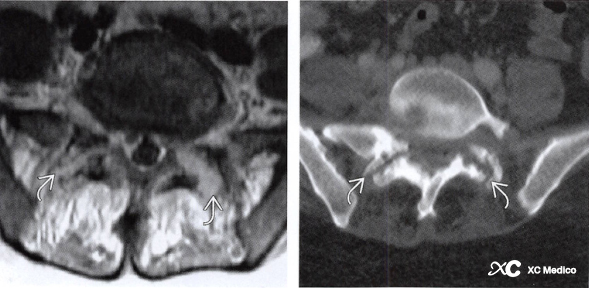

Спинальная подагра характеризуется отложениями монокристаллических кристаллов урата (MUCS) в позвоночнике. Спинальная подагра в основном влияет на поясничный позвоночник. Рентгенограммы показывают неспецифические проявления, а КТ лучше характеризует эрозию кости склеротическими краями. МРТ -проявления неспецифичны.

Примечание: CT Plain Scan показывает сужание сустава и двустороннее разрушение суставной поверхности. Артроцентез необходим для подтверждения диагноза.